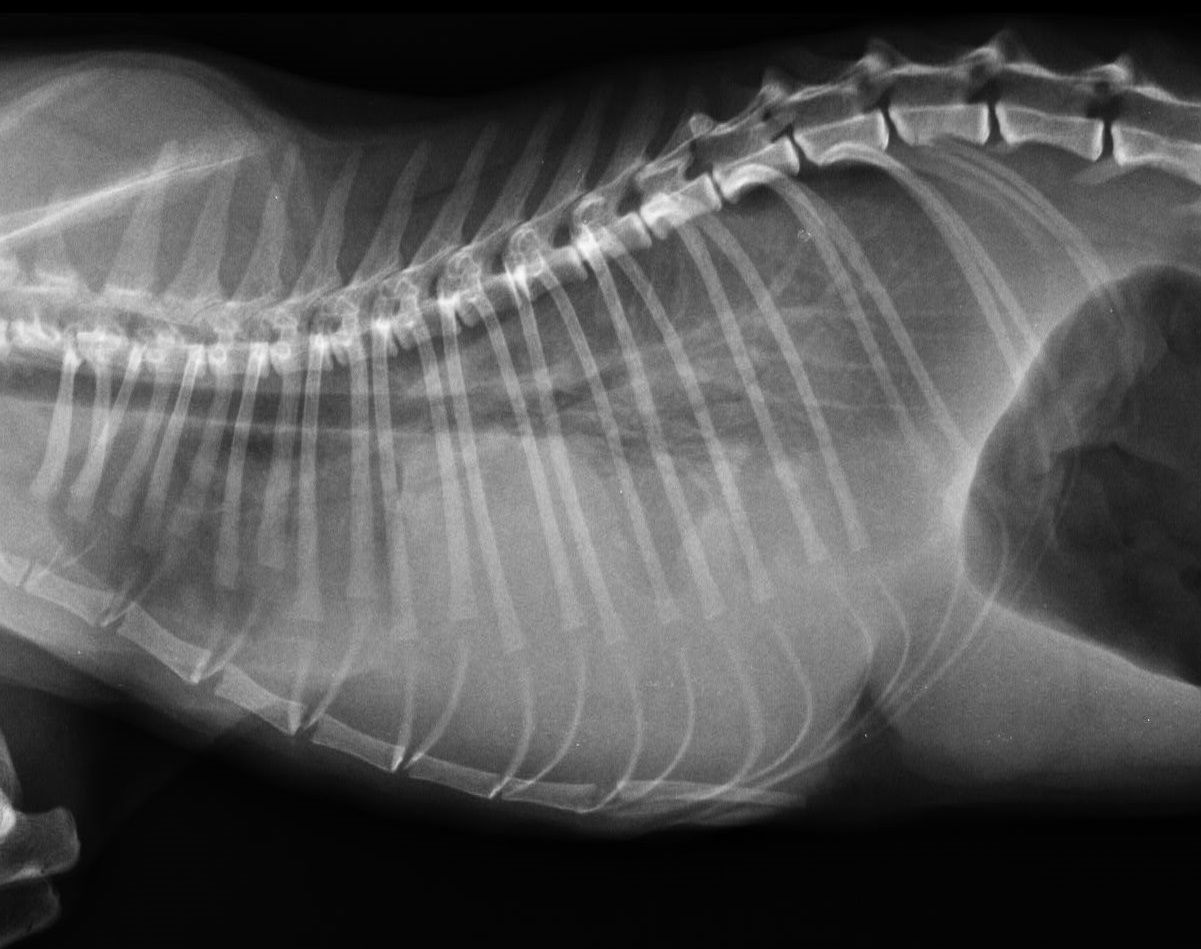

L'imagerie reste un examen complémentaire de choix en médecine vétérinaire. De nouvelles techniques se sont développées comme le Scanner ou l'IRM que l'on peut dorénavant retrouver dans des Centres Hospitaliers Vétérinaires. Cependant, la radiologie ainsi que l'échographie demeurent des examens de première intention qui permettent de diagnostiquer un certain nombre de pathologies le jour de la consultation si nécessaire.

La clinique est équipée d'un générateur radio ainsi que d'un développement numérique. Ce type de développement est rapide, sans utilisation de produits chimiques et permet d'obtenir les images sur un écran d'ordinateur. La définition des radios est ainsi meilleure. Nous pouvons aussi facilement vous faire parvenir les radios de votre animal ou les transférer à un confrère le cas échéant par mail.

- Radios classiques